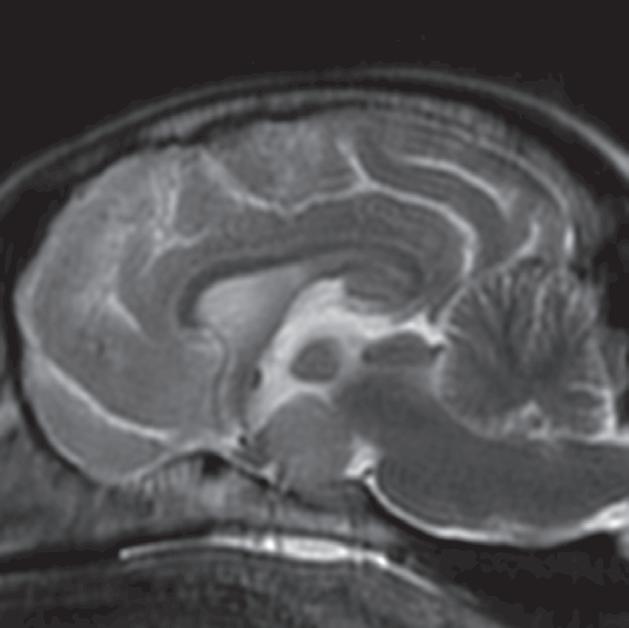

Rycina 2.9.12. Gruczolak przysadki (pies) MR

Badanie wykonano u 14-letniej, kastrowanej samicy szpica z przechyleniem głowy i występującym od niedawna chodzeniem w kółko w prawą stronę. Ryciny a–c to reprezentatywne obrazy w płaszczyźnie poprzecznej na poziomie dołu przysadki. Ryciny d–f to analogiczne obrazy w płaszczyźnie strzałkowej. Przysadka mózgowa była znacznie powiększona (wysokość = 10 mm, szerokość = 10 mm), izointensywna w obrazach T1-zależnych (a, d) i łagodnie hiperintensywna w obrazach T2-zależnych (b, e) w porównaniu z istotą szarą głęboką. Stwierdzono również poszerzenie układu komorowego (wentrikulomegalię), które może wynikać z częściowej niedrożności. Przysadka uległa jednorodnemu wzmocnieniu kontrastowemu (c, f), a w badaniu pośmiertnym wykazano, że miała postać dobrze odgraniczonej, kulistej masy (g). Potwierdzono, że zmiana była makrogruczolakiem przysadki